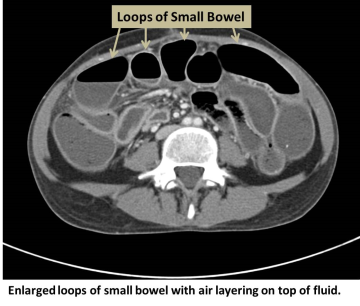

Diagnosis

In addition to the physical exam, the physician will determine the location and type of blockage using

- CT scan